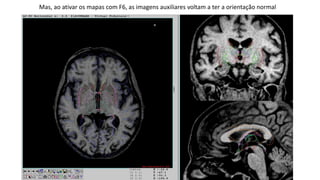

As imagens auxiliares na direita da tela continuam com orientação pouco comum

Mas, ao ativar os mapas com F6, as imagens auxiliares voltam a ter a orientação normal